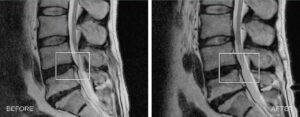

Slipped disc

SPINAL DECOMPRESSION is a mechanical therapy that uses automated decompressive forces to mobilise joints, relieve the pressure over neuro-spinal structures, and relax and elongate soft tissues.

The SPINAL DECOMPRESSION promotes a new way forward to precise targeting of the therapy into impaired segments of the spine and innumerable options for the treatment of lower back pain of any origin.